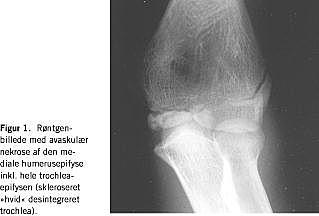

Ved den kliniske undersøgelse efter det aktuelle traume fandt man i forhold til den raske albue en let aktiv bevægeindskrænkning på fem grader grundet smerter. Den passive bevægelighed var normal, men med let ømhed ved fuld supination. En røntgenundersøgelse viste et mindre intraartikulært hæmatom og ingen frakturer, men avaskulær nekrose af den mediale humerusepifyse inkl. hele trochlea-epifysen (skleroseret »hvid« desintegreret trochlea) (Figur 1 ).